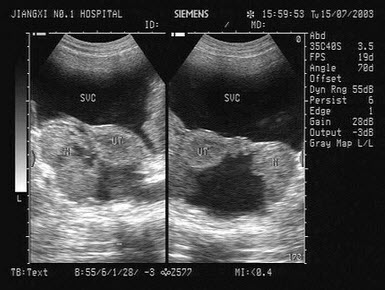

C.脐带绕颈3周

该食管超声心动图显示图像为()

A.房间隔缺损(上腔型)

B.房间隔缺损(下腔型)

C.房间隔缺损(中央型)

D.房间隔缺损(混合型)

E.冠状静脉窦扩张